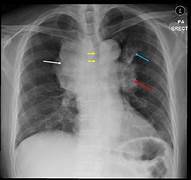

O que esse raio x sugere e quais são as os sinais presentes? Derrame pleural; Imagem em menisco, parabola de Demousiau, opacificação do espaço pleural, deslocamento do diafragma, imagem em menisco, fissuras pleurais e leve deslocamento do mediastino.

Quais são os achados radiológicos do derrame pleural? O que pode causar a doença? -Presença de muito líquido no espaço pleural -Obliteração do seio costofrênico (preenchimento do espaço entre as costelas e o diafragma) -Imagem em menisco -Elevação da cúpula diafragmática -Lawrell pode deslocar o líquido; Tuberculose e neoplasias (Doença pleural), insuficiência cardíaca e congestiva (Doença sistêmica)

Quais são os sinais radiológicos de derrame pleural? Opacificação do espaço pleural, sinal do menisco, deslocamento do diafragma e fissuras pleurais.